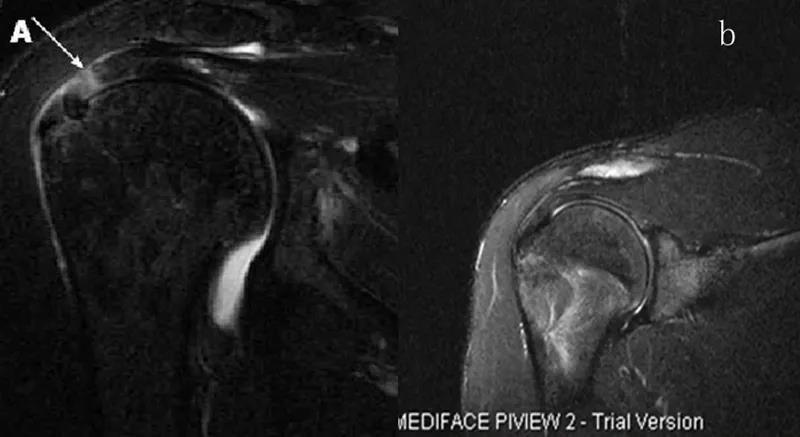

图21 斜冠状位(临床常用)a.T2,b.T1